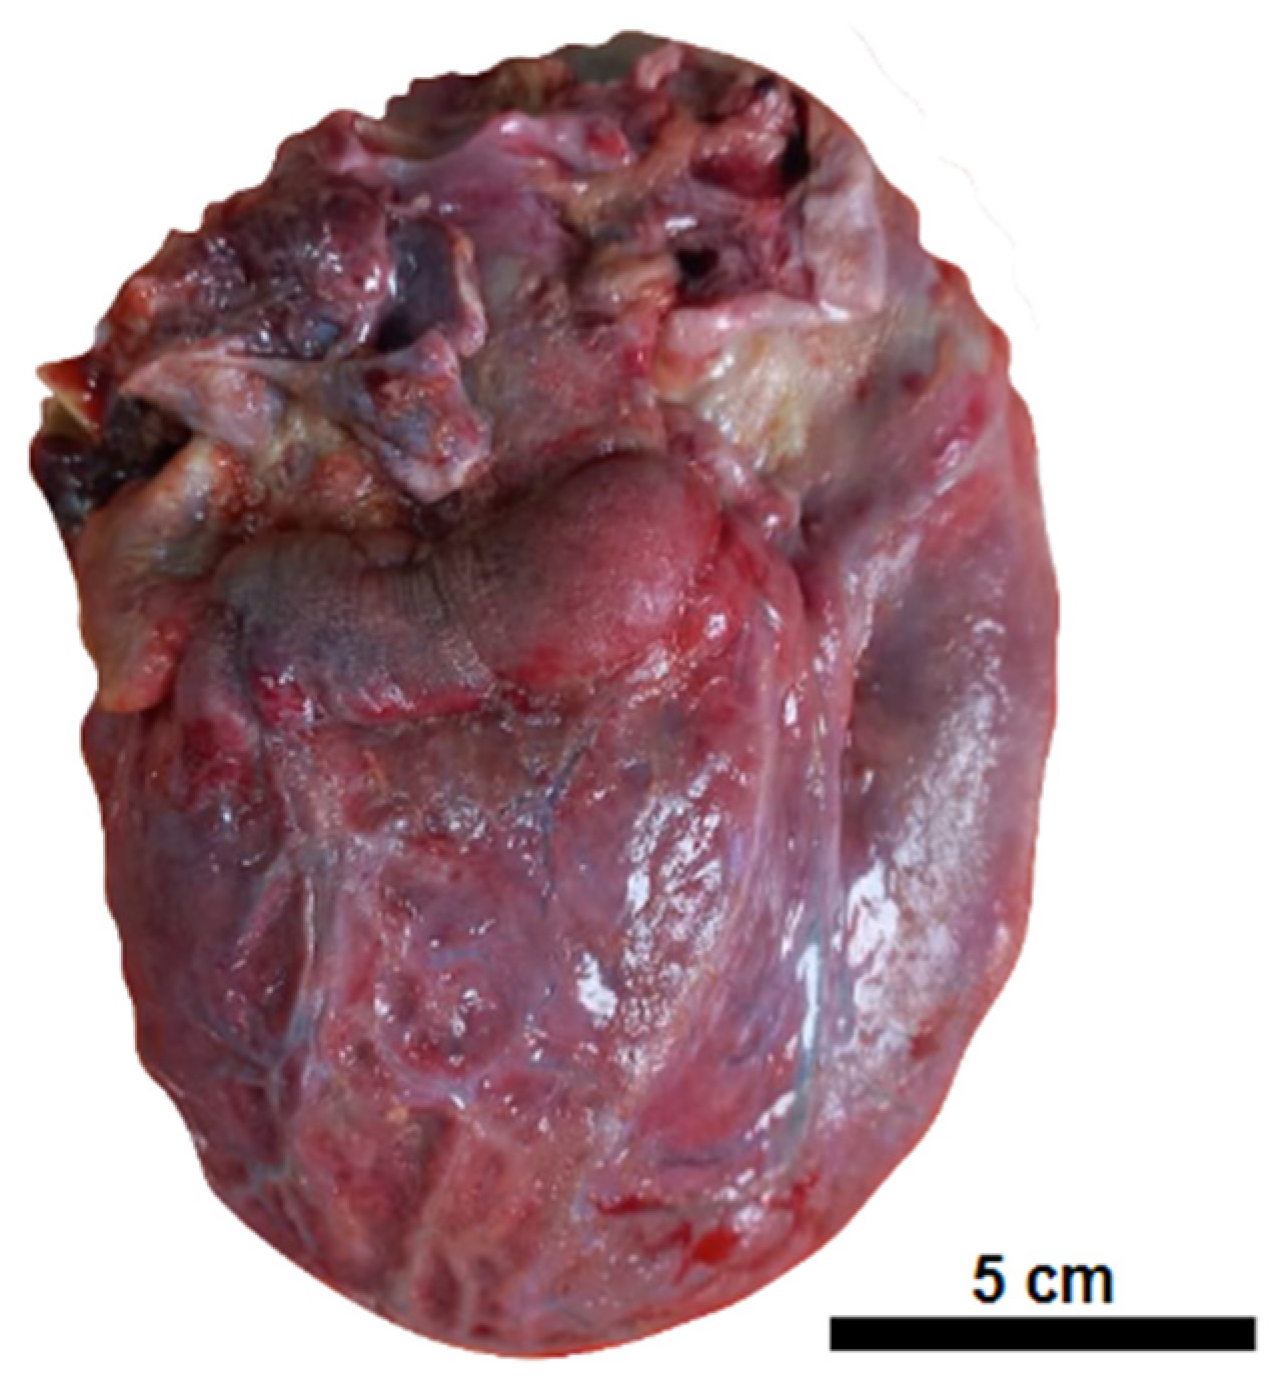

| Macroscopic findings | Edema and tonsil herniation. | Fibrinous perimyocarditis with hemorrhage. Valves unchanged | Edema and congestion. | Moderate steatosis hemorrhagic appearance | Signs of shock. |

| Microscopic findings | Tissue edema. Reactive gliosis. Vascular thromboembolism. | Pericardium: intense deposition of fibrin, red blood cells, and inflammatory cells. Myocardium: interfascicular edema, coagulative myocyte necrosis. Hemorrhage and inflammatory infiltrate rich in macrophages and t-cells. Aschoff’s nodules and/or Anitschkow’s cells: not observed. Endocardium: slight loose fibrosis and inflammatory infiltrate. | Parenchymal hemorrhage. Vascular thromboembolism. Inflammatory infiltrate of lymphocytes, neutrophils, and xanthomatous macrophages. | Hemorrhagic necrosis. Vascular thromboembolism. Microvesicular steatosis. | Acute tubular necrosis. |